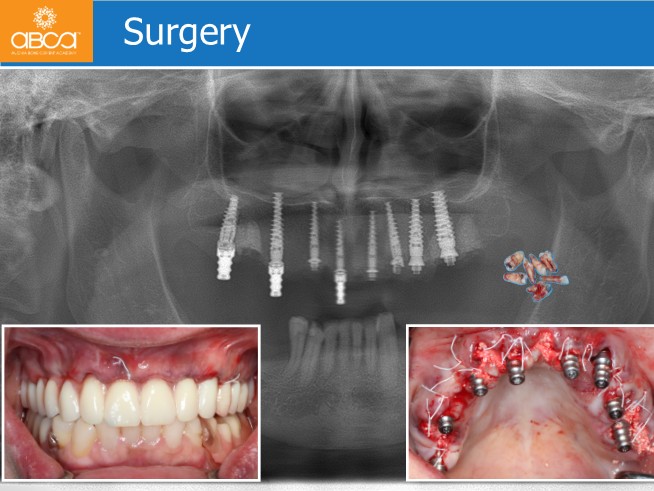

The first surgery is an All-on-X in the upper jaw. After a short period of healing, it was our objective to deliver the final prosthetics 7 months post-op.

Next is the rehabilitation of the upper jaw with a screw retained “I”BAR. Composite build up of the lower incisors and canines then rehab with a removable cromo cobalt denture on the lower jaw.